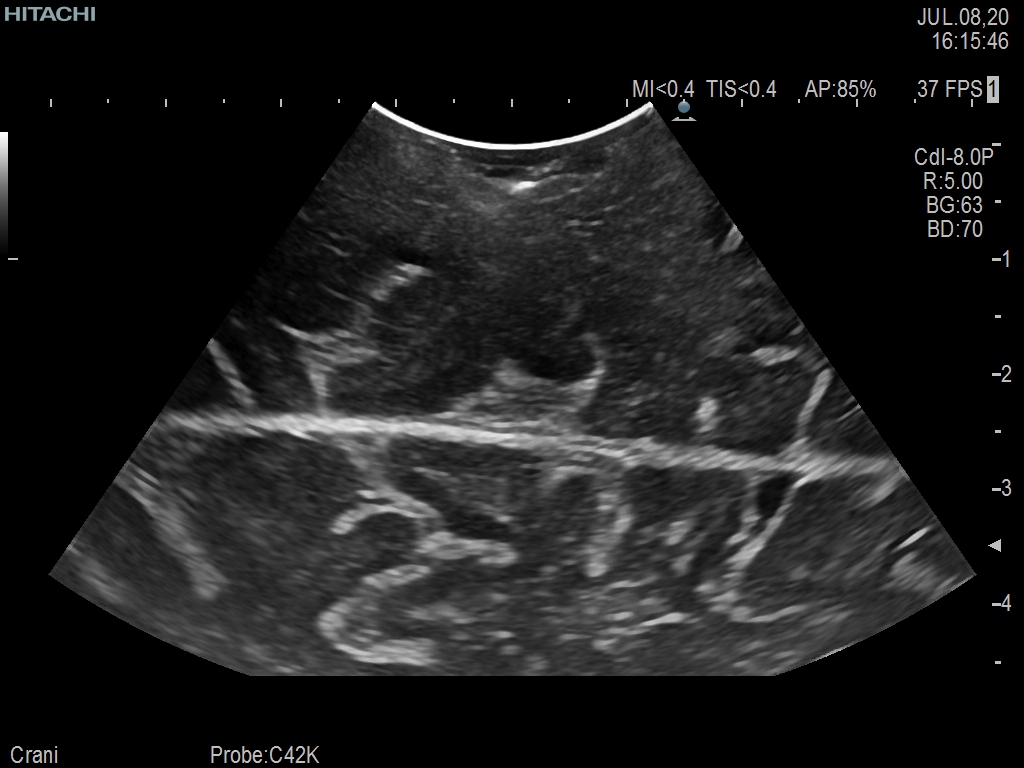

Superior guidance for all applications

Fujifilm Healthcare Americas is committed to designing tools that help surgeons navigate inside the human body and provide the necessary information to immediately make critical surgical decisions.

Fujifilm Healthcare's dedication to Surgeons provides outstanding ultrasound technology, professional support and the specialized tools necessary to best perform comprehensive real-time ultrasound imaging in Breast Surgery, General Surgery, Laparoscopic Surgery, Neurosurgery, Robotic Surgery and Surgical Oncology.

Recognized for our outstanding image quality, outstanding system reliability and intuitive use of cutting edge technology, Fujifilm Healthcare remains the standard in the field of Surgery.

Recognized for our outstanding image quality, outstanding system reliability and intuitive use of cutting edge technology, Fujifilm Healthcare remains the standard in the field of Surgery.